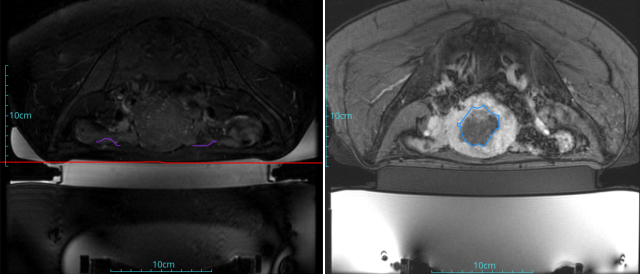

子宮肌瘤

患者信息:女,38

診斷:子宮肌瘤

腫瘤尺寸:約為38*40*42mm

ROT深度:腫瘤的ROT中心距離皮膚62mm

術后評估:術后造影增強圖像顯示消融區(qū)域(右側)與腫瘤區(qū)域(左側)重合度較好,且非灌注區(qū)域連續(xù)且一致。

結論:對該腫瘤具有非常好的消融效果,治療過程中,溫度上升曲線符合預期,每個被治療的靶點240CEM區(qū)域體積較大、外形飽滿、連續(xù)。病灶消融良好,NPV體積比約87.88%。